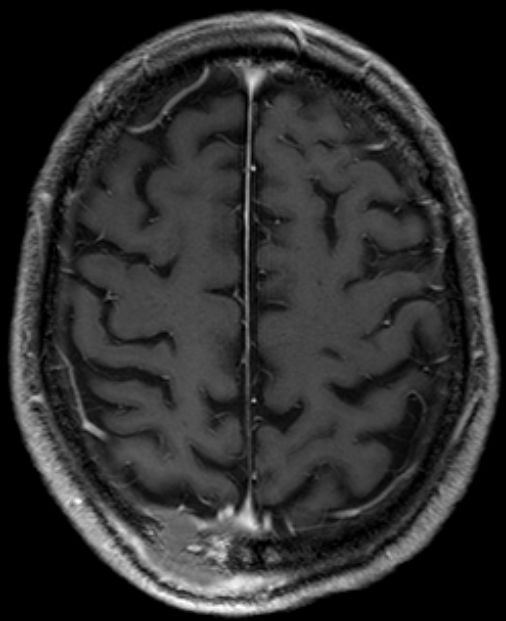

Kalotte |

46-jähriger Mann, der sich vor 6 Wochen am Hinterkopf gestoßen habe. Die Schwellung sei nicht zurückgegangen. Er habe zusätzlich Kopfschmerzen bekommen.

Das CT zeigt lediglich eine Füllung des Liquprspaltes links dorsal.Der Befund erwies sich DLBCL, welches die Dura infiltriert hatte. ![]() |

Im T1-gewichteten MRT ist der Tumor

zu erkennen.![]() | ||